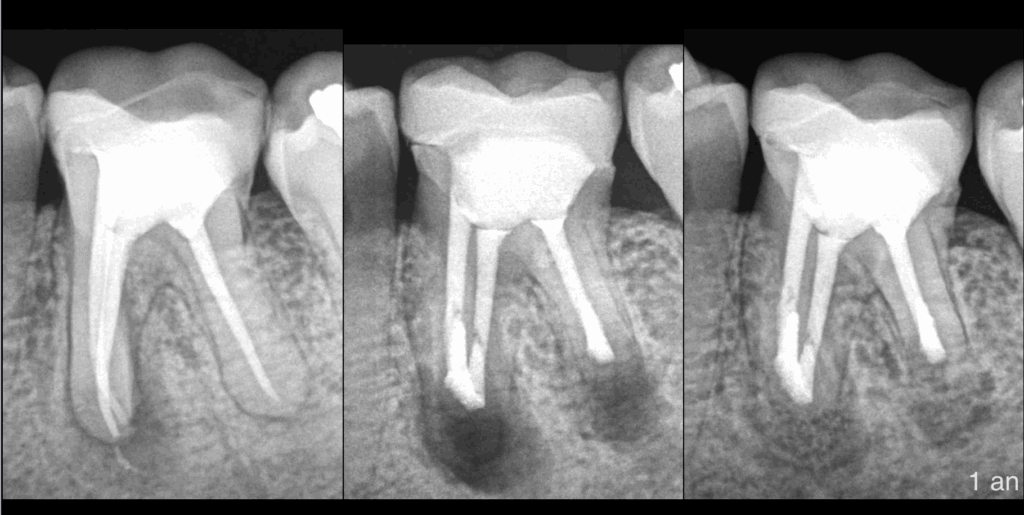

𝐏𝐮𝐥𝐩𝐞 𝐩𝐫𝐞́𝐜𝐞́𝐝𝐞𝐦𝐦𝐞𝐧𝐭 𝐭𝐫𝐚𝐢𝐭𝐞́𝐞, 𝐩𝐚𝐫𝐨𝐝𝐨𝐧𝐭𝐢𝐭𝐞 𝐚𝐩𝐢𝐜𝐚𝐥𝐞 𝐚𝐬𝐲𝐦𝐩𝐭𝐨𝐦𝐚𝐭𝐢𝐪𝐮𝐞 𝐝𝐞𝐬 𝐫𝐚𝐜𝐢𝐧𝐞𝐬 𝐌 & 𝐃

❓ 𝐑𝐞𝐭𝐫𝐚𝐢𝐭𝐞𝐦𝐞𝐧𝐭 𝐜𝐚𝐧𝐚𝐥𝐚𝐢𝐫𝐞 𝐨𝐮 𝐜𝐡𝐢𝐫𝐮𝐫𝐠𝐢𝐞 𝐞𝐧𝐝𝐨𝐝𝐨𝐧𝐭𝐢𝐪𝐮𝐞 ?

🦷 𝐏𝐫𝐨𝐭𝐡𝐞̀𝐬𝐞 𝐜𝐨𝐥𝐥𝐞́𝐞 𝐚𝐝𝐚𝐩𝐭𝐞́𝐞, 𝐭𝐫𝐚𝐢𝐭𝐞𝐦𝐞𝐧𝐭 𝐜𝐚𝐧𝐚𝐥𝐚𝐢𝐫𝐞 𝐫𝐞́𝐩𝐨𝐧𝐝𝐚𝐧𝐭 𝐚𝐮𝐱 𝐜𝐫𝐢𝐭𝐞̀𝐫𝐞𝐬 𝐝𝐞 𝐪𝐮𝐚𝐥𝐢𝐭𝐞́ 𝐞𝐧 𝐦𝐞́𝐬𝐢𝐚𝐥 -> 𝐢𝐧𝐝𝐢𝐜𝐚𝐭𝐢𝐨𝐧 𝐝𝐞 𝐦𝐢𝐜𝐫𝐨𝐜𝐡𝐢𝐫𝐮𝐫𝐠𝐢𝐞 𝐞𝐧𝐝𝐨𝐝𝐨𝐧𝐭𝐢𝐪𝐮𝐞 𝐝𝐞𝐬 𝐫𝐚𝐜𝐢𝐧𝐞𝐬 𝐌 𝐞𝐭 𝐃 !

📌 𝐄𝐧 𝐝𝐢𝐬𝐭𝐚𝐥 𝐥’𝐨𝐛𝐭𝐮𝐫𝐚𝐭𝐢𝐨𝐧 𝐜𝐚𝐧𝐚𝐥𝐚𝐢𝐫𝐞 𝐬𝐞𝐦𝐛𝐥𝐞 𝐜𝐨𝐮𝐫𝐭𝐞. 𝐌𝐚𝐢𝐬 𝐞𝐧 𝐦𝐞́𝐬𝐢𝐚𝐥, 𝐪𝐮’𝐞𝐬𝐭-𝐜𝐞 𝐪𝐮𝐢 𝐩𝐞𝐮𝐭 𝐞𝐱𝐩𝐥𝐢𝐪𝐮𝐞𝐫 𝐪𝐮𝐞 𝐥’𝐢𝐧𝐭𝐞𝐫𝐯𝐞𝐧𝐭𝐢𝐨𝐧 𝐩𝐫𝐞́𝐜𝐞́𝐝𝐞𝐧𝐭𝐞 𝐧’𝐚𝐢𝐭 𝐩𝐚𝐬 𝐞́𝐭𝐞́ 𝐞𝐟𝐟𝐢𝐜𝐚𝐜𝐞 ?

👉 𝐋’𝐚𝐧𝐚𝐭𝐨𝐦𝐢𝐞 𝐜𝐚𝐧𝐚𝐥𝐚𝐢𝐫𝐞 ! 𝐁𝐢𝐞𝐧 𝐩𝐥𝐮𝐬 𝐜𝐨𝐦𝐩𝐥𝐞𝐱𝐞 𝐪𝐮’𝐞𝐥𝐥𝐞 𝐧’𝐚𝐩𝐩𝐚𝐫𝐚𝐢̂𝐭 𝐫𝐚𝐝𝐢𝐨𝐠𝐫𝐚𝐩𝐡𝐢𝐪𝐮𝐞𝐦𝐞𝐧𝐭.

🧠 𝐀𝐯𝐞𝐜 𝐧𝐨𝐭𝐚𝐦𝐦𝐞𝐧𝐭 𝐥𝐚 𝐩𝐫𝐞́𝐬𝐞𝐧𝐜𝐞 𝐝’𝐮𝐧 𝐢𝐬𝐭𝐡𝐦𝐞 𝐪𝐮𝐢 𝐫𝐞𝐣𝐨𝐢𝐠𝐧𝐚𝐢𝐭 𝐥𝐞𝐬 𝐜𝐚𝐧𝐚𝐮𝐱 𝐌𝐕 𝐞𝐭 𝐌𝐋.